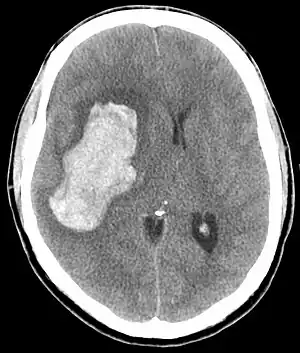

CT scan of an intracranial hemorrhage, a possible complication of hypertensive emergency.

The most common presentations of hypertensive emergencies are cerebral infarction (25%), pulmonary edema (23%), hypertensive encephalopathy (16%), and heart failure (12%).[8] Less common include intracranial bleeding, aortic dissection, and pre-eclampsia or eclampsia.[9]

In the brain, hypertensive encephalopathy - characterized by hypertension, altered mental status, and swelling of the optic disc - is a manifestation of the dysfunction of cerebral autoregulation. Cerebral autoregulation is the ability of the blood vessels in the brain to maintain a constant blood flow. People with chronic hypertension can tolerate higher arterial pressure before their autoregulation system is disrupted. Hypertensives also have an increased cerebrovascular resistance which puts them at greater risk of developing cerebral ischemia if the blood flow decreases into a normotensive range. On the other hand, sudden or rapid rises in blood pressure may cause hyperperfusion and increased cerebral blood flow, causing increased intracranial pressure and cerebral edema, with increased risk of intracranial bleeding.[11]

Consequences of hypertensive emergency result after prolonged elevations in blood pressure and associated end-organ dysfunction. Acute end-organ damage may occur, affecting the neurological, cardiovascular, kidney, or other organ systems. Some examples of neurological damage include hypertensive encephalopathy, cerebral infarction, subarachnoid hemorrhage, and intracranial bleeding. Cardiovascular damage can include myocardial ischemia, acute left ventricular dysfunction, pulmonary edema, and aortic dissection. Other end-organ damage can include acute kidney failure, retinopathy, eclampsia, and microangiopathic hemolytic anemia.